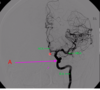

Which arteries do the arrows point to? [1]

Lenticulostiate arteries